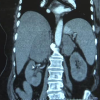

ELAZIĞ - Elazığ'da 8 çocuk annesi ve 24 torun sahibi 71 yaşındaki Elmast Carfi, Laparoskopik cerrahi yöntemi ile sağlığına kavuştu. Elazığ'da 8 çocuk annesi ve 24 torun sahibi 71 yaşındaki Elmast Carfi, halsizlik şikayeti ile hastaneye başvurdu. Tümör taraması yapılan Elmast ninenin böbrek bezlerinde büyüme tespit edildi. Sağ böbrek bezinde 10 ve sol böbrek bezinde 7 santimlik bir büyüme görülen Elmast nine, Elazığ Medical Park Elazığ Hastanesi'nde Laparoskopik cerrahi (kapalı ameliyat) yönetimi ile ameliyat olarak sağlığına kavuştu. 71 yaşında 24 tane toruna sahip olduğunu dile getiren Elmast Carfi, "50 gündür hastanelerde geziyorum. Allah'a şükür bu doktoruma rastladım. Ameliyat yaptılar ve çok iyi geçti. Çok memnunum. O kadar gezdim, kimse ameliyat yapmadı. Hiç gezemiyordum. Lavaboya bile gidemiyordum, şimdi çok iyiyim" dedi. Elmast Carfi'nin genel durum bozukluğu ve halsizlik şikayetiyle başka hastanelere başvuruda bulunduğu belirten Üroloji Uzmanı Op. Dr. Serhat Yentür, "Tümör açısından taranırken her iki böbrek üstü bezinin büyüdüğü fark ediliyor. Sonrasında bize yönlendirdiler. Hormon salgılamayan bir adenom şeklinde büyümesi vardı. Birde hormon salgılayan ve hiç hormon salgılamayan formları var. Böbrek üstü bezlerinden adrenalin, noradrenalin, dopomin, kortizon ve aldosteron dediğimiz vücudun çalışmasıyla ilgili çok önemli hormonların salınıma sebep açar. Bu hastamızda hormonların aşılı salınması veya salınmaması gibi söz konusu değildi. Tamamen adenematoz bir büyüme olduğunu düşünüyoruz. Normalde bu büyüklükteki böbrek üstü bezlerinde açık cerrahi yapılırken, biz bu hastamıza Laparoskopik cerrahi yaptık. Kapalı yöntemle bu hastamızı ameliyat ettik" diye konuştu. Açık ameliyat olmuş olsaydı hastanın her iki yan tarafından en az 12 santimetrelik kesiler oluşacağını vurgulayan Yentür, "Hastamızın vücudunun yarısını kesmiş olacaktık. 3'üncü günden sonra taburcu edilecek duruma geldi. İlaçlarının dozlarını ayarlamaya çalışıyoruz. Onda sonra taburcu edeceğiz. Hasta çok erken sürede ayağa kalkıyor. Yaraları daha çabuk iyileşiyor. Ağrıları ise çok az seviyede oluyor. Normal şartlarda 10 gün kadar yatıp yaraları iyileşene kadar izlememiz lazımken hastamızı 4'üncü gününde taburcu edeceğiz. Normalde böbrek üstü bezleri bir santimetreyken hastamızın sağ 10 santimetre, sol tarafı ise 7 santimetre şeklindeydi" diye bilgi verdi.